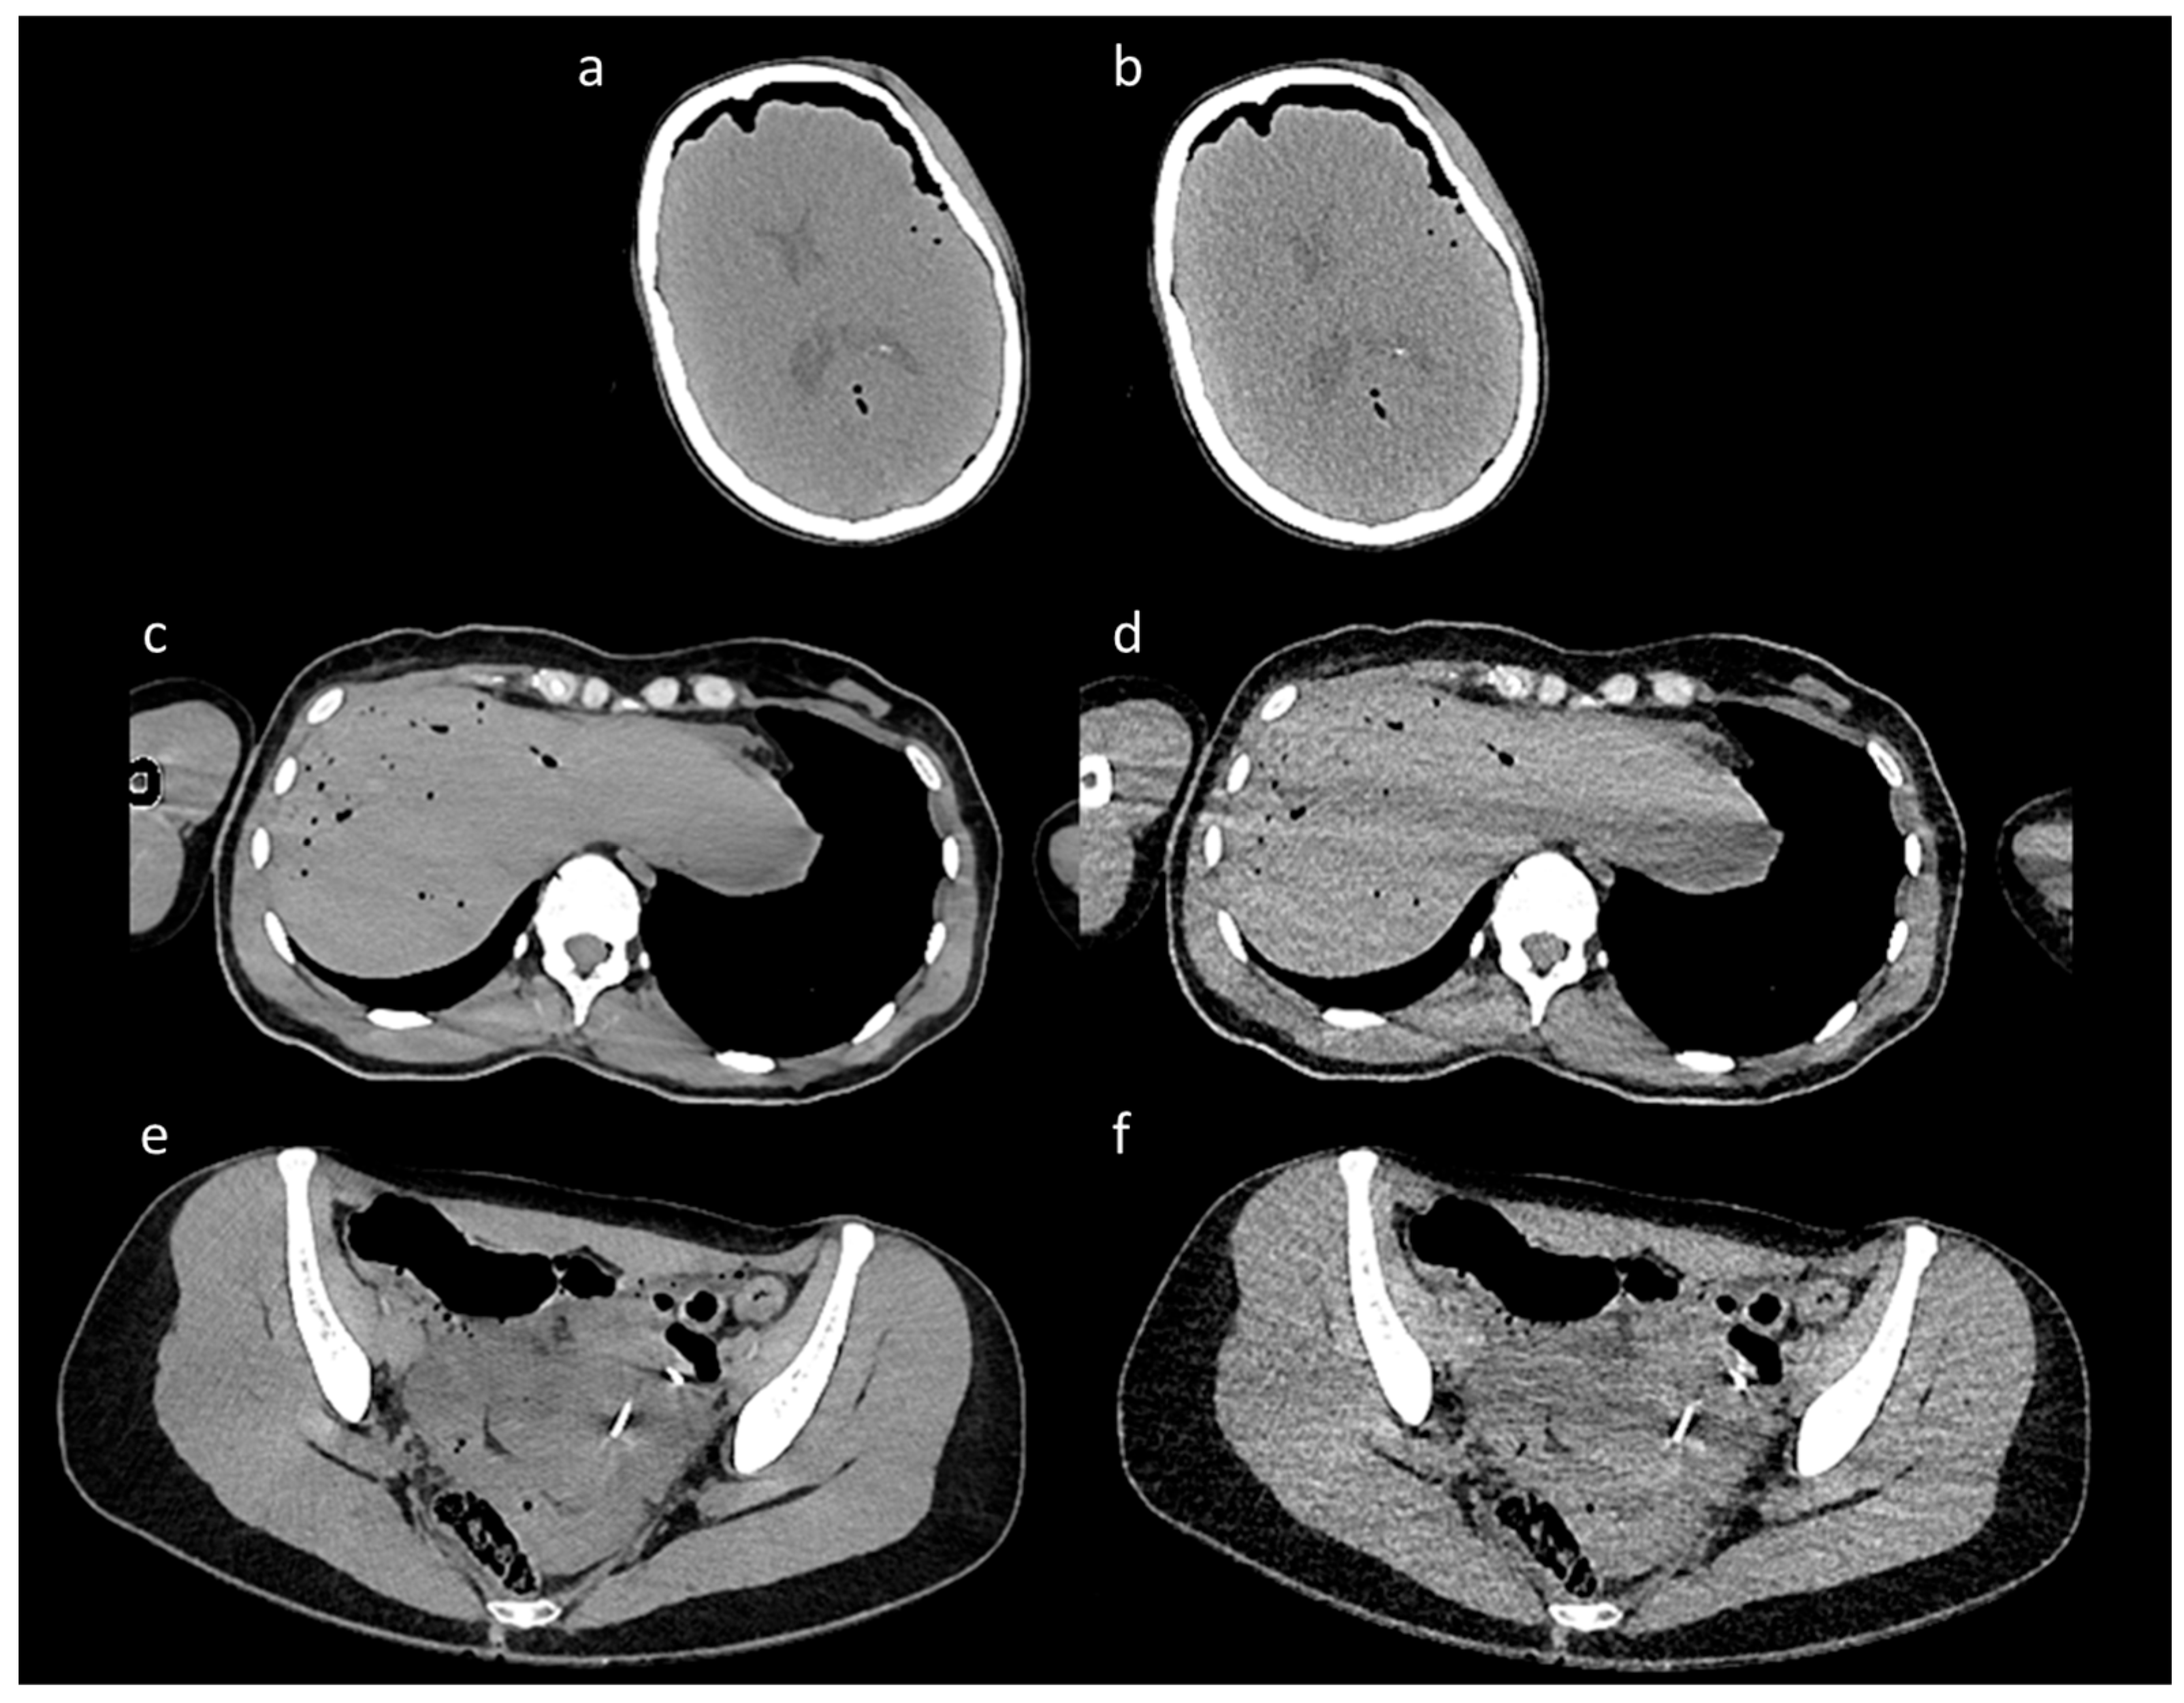

- Increased PSNR from an average of 30.78 in the LQ images to 31.32 in the ErisNet-processed images, with a SD of 3.69;

- Substantially reduced MSE from 73.45 in the LQ images to 64.70 in the ErisNet-processed images;

- Increased the SSIM values from 0.92 to 0.94;

- Increased VIF from 0.47 in LQ images to 0.49;

- Did not compromise EPI, which was 0.97 in LQ images and 0.97 with ErisNet;

- Decreased noise variance from 73.43 in LQ images to 64.69 in ErisNet;